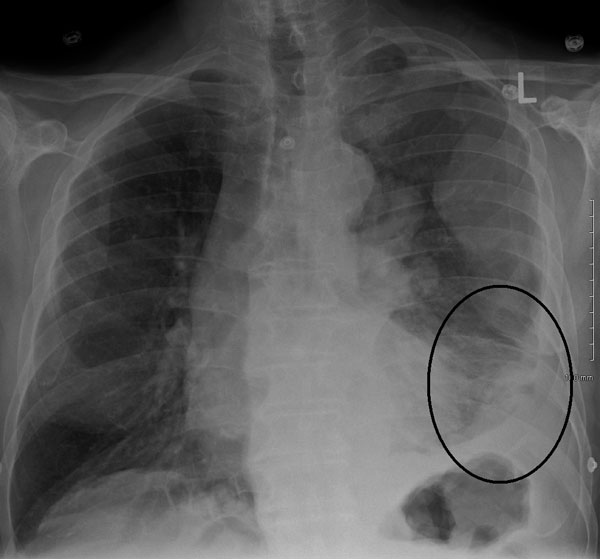

X-rays

X-rays can reveal the presence of fluid accumulation, thickening of the pleura (lining of the lungs), or any mass indicative of mesothelioma.